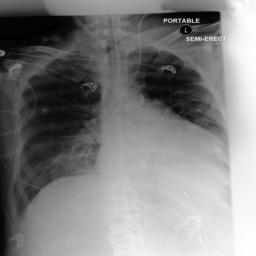

5.2 Visualization of attention weights

Fig. 5 presents a qualitative visualization of the learned word-to-region correspondences facilitated by our AGA framework. The top row shows the original medical images, including both chest X-rays (CXR) and endoscopic ultrasound (EUS) images. The bottom row displays the corresponding heatmaps generated by our model, where warmer colors denote higher activation weights, indicating stronger associations between specific image regions and the given medical concepts. For Atelectasis and Pneumonia, the model focuses on appropriate pulmonary regions, demonstrating strong localization aligned with radiological pathology. For the SMTs domain, terms like low-echoic mass and protruded into the cavity activate precisely the relevant interior structures of the lesion in EUS images. The distinct and interpretable activation patterns validate the effectiveness of our AGA mechanism in achieving fine-grained multimodal alignment.

Atelectasis

Pneumonia